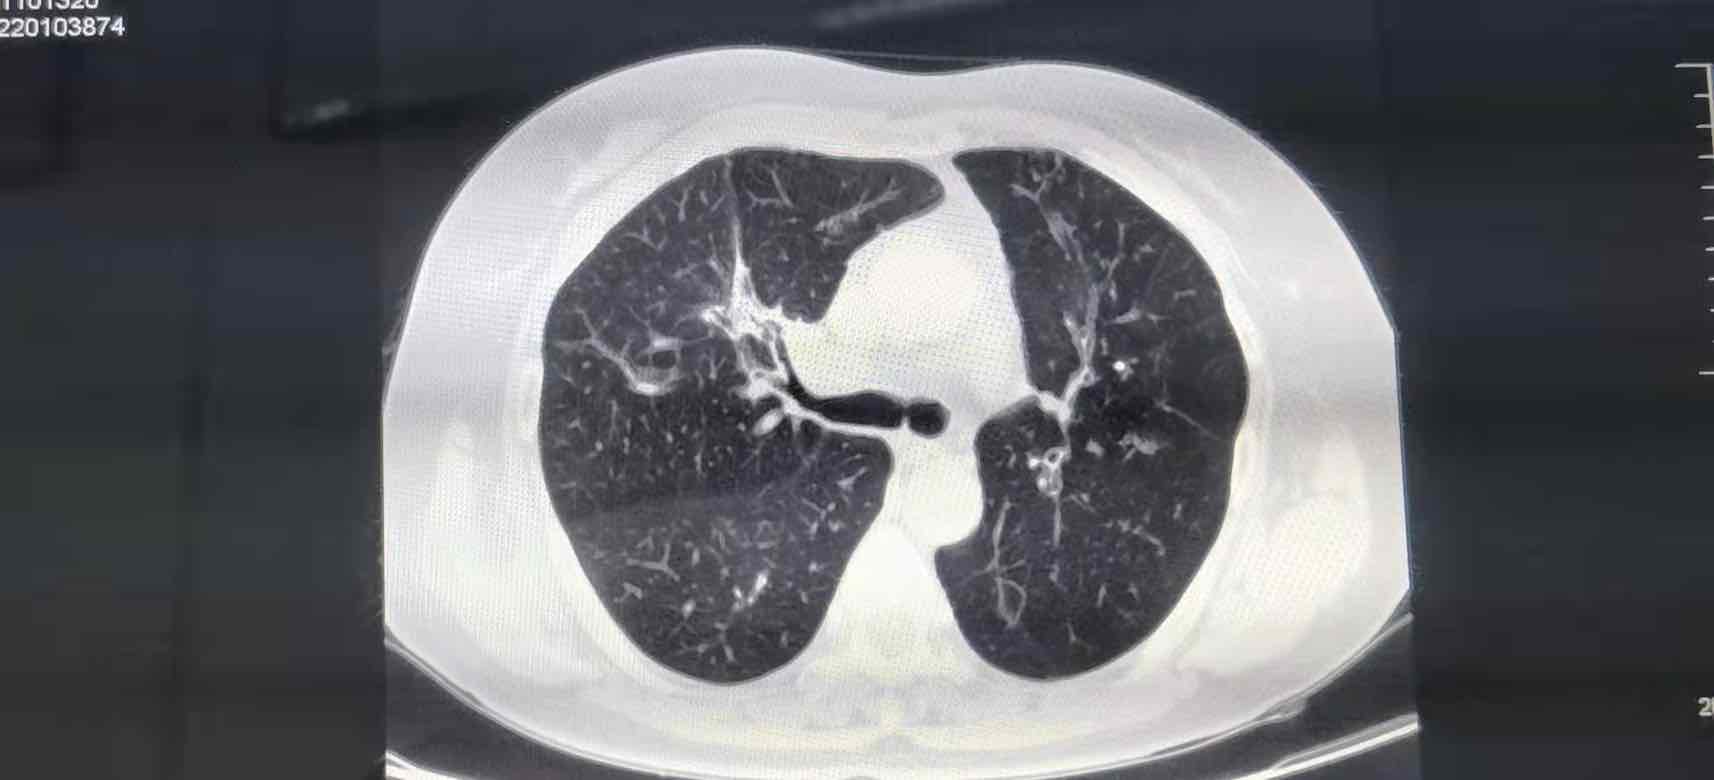

母亲吃克唑替尼1个月效果明显

1.11日检查结果病灶明显减少,后天第二次复查希望病灶再次减小,争取手术机会

这是服用克唑替尼一个月的效果

1.11日病灶2.8✖️3.5